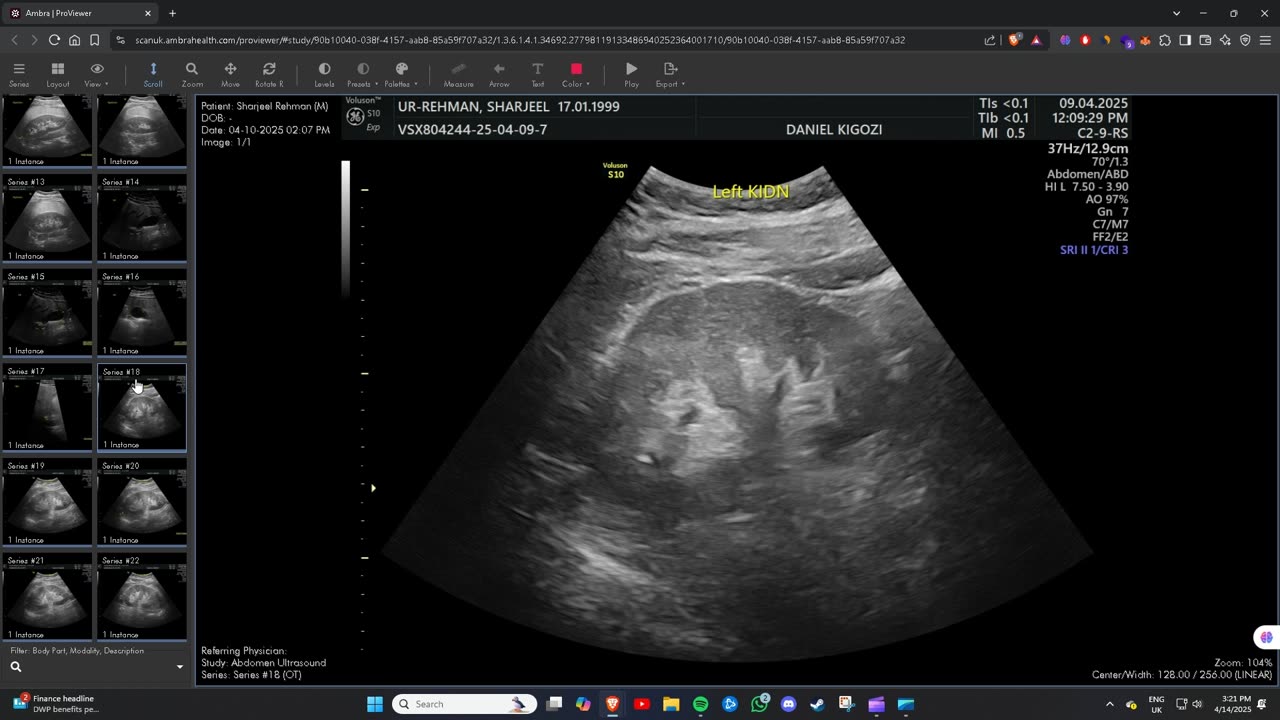

Ultrasound Scan Images

Here are the ultrasound scan images I received from Scan.com, which were done by Ultrasound Plus Docklands E14 9UD on April 9, 2025.

Everything is documented for the safety of both myself and others.